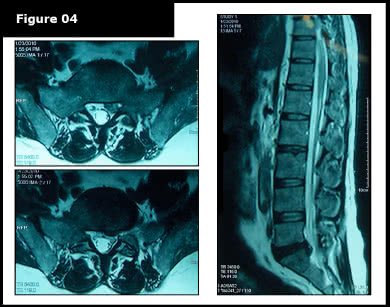

The patient had previously undergone two MRI scans, the first on December 29, 2009, and a second on January 23, 2010 (Figures-3 and 4).

A comparative review of the MRI scans revealed a worsening of the disc bulge observed in December 2009. The condition had progressed to a moderate disc extrusion, which significantly compressed the spinal cord (thecal sac) and S1 nerve root.

To address the condition, NSD Therapy® was recommended to promote recovery and improve function. Due to the severity of the disc condition, the patient underwent 25 therapy sessions of NSD Therapy®, administered five times per week for five weeks.